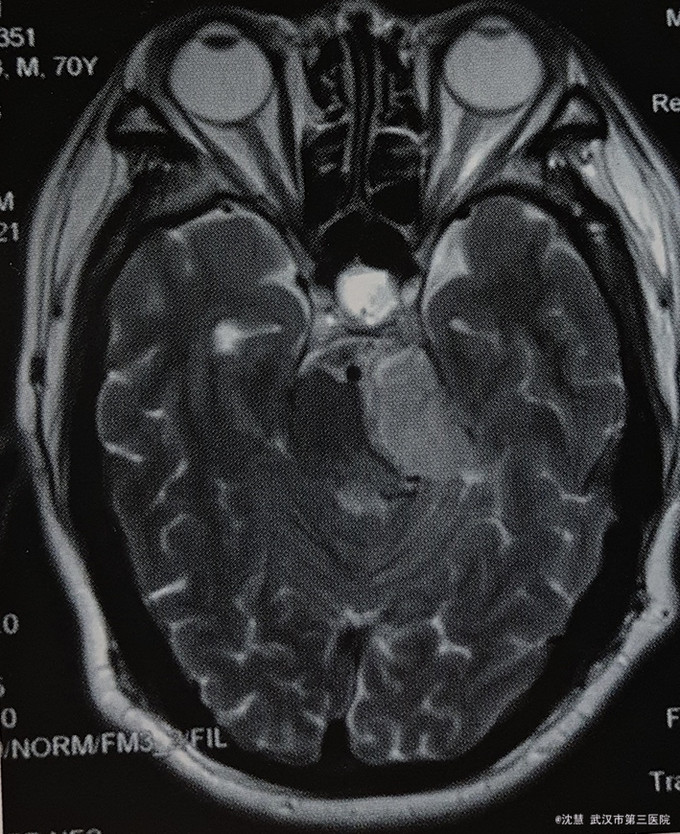

患者男,70岁,主因左耳听力减退20余年,行走不稳半月入院。患者20余年前出现左耳听力减退,无其他不适。半月前出现行走不稳,向左侧倾倒,伴左侧耳鸣、左侧面部麻木,无意识障碍、头痛,无吞咽困难、饮水呛咳、声音嘶哑等。

查体:生命体征平稳,心肺腹体检无明显异常。专科检查:左眼外展稍受限,左侧咀嚼肌力量减弱,左侧颜面部痛温觉减退,左侧听力减退,左侧指鼻、指指及跟膝胫实验欠协调,Romberg征阳性。 影像学:头部MRI:左侧桥小脑角占位,脑干受压。

诊断:桥小脑角肿瘤 治疗:全麻下左侧桥小脑角区脑膜瘤切除术 病理:(左侧桥小脑角区)脑膜瘤(WHO I级)